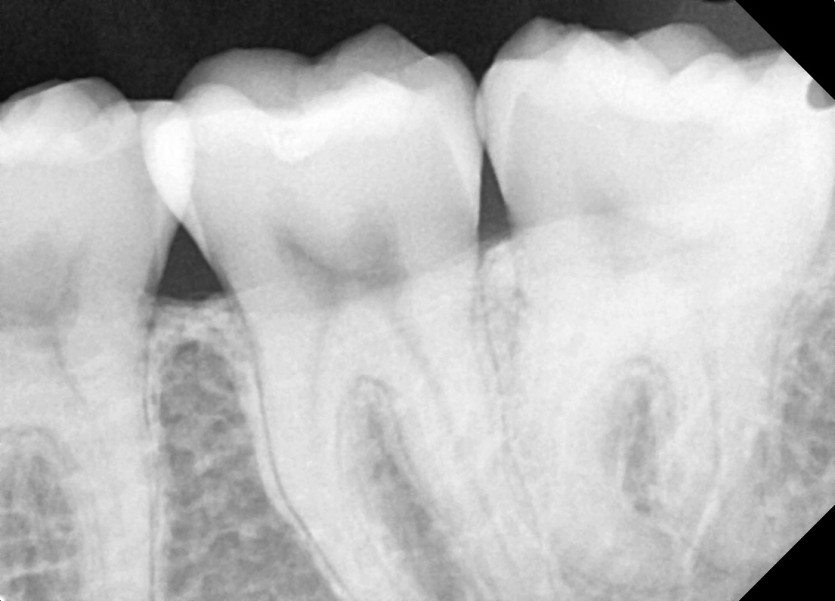

#28,38 사랑니 발치

구강 외과 전문의가 당일 발치했습니다.